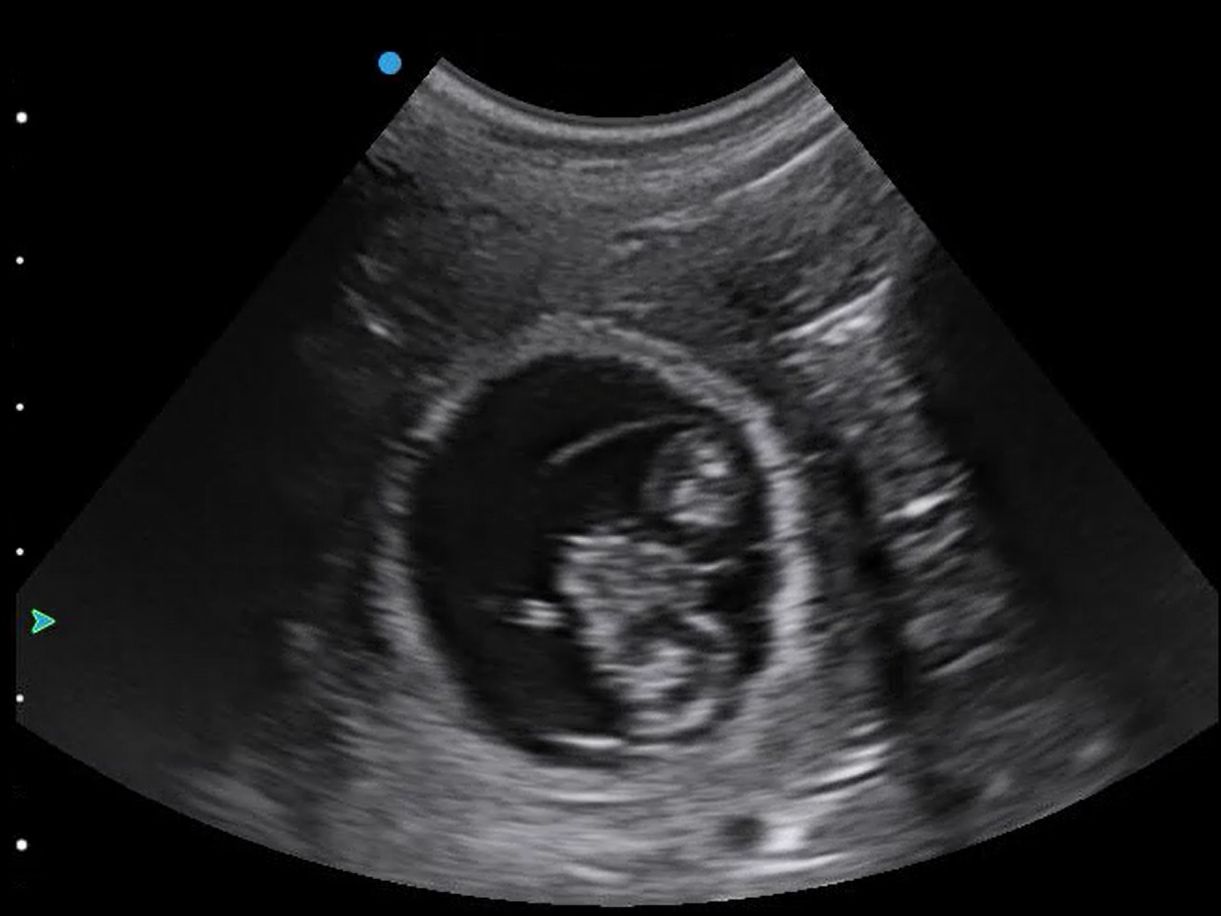

This beautiful chihuahua is around 30 days pregnant, with at least four healthy puppies seen. We saw the flicker of heartbeats in each sac, and lovely clear amniotic fluid inside.